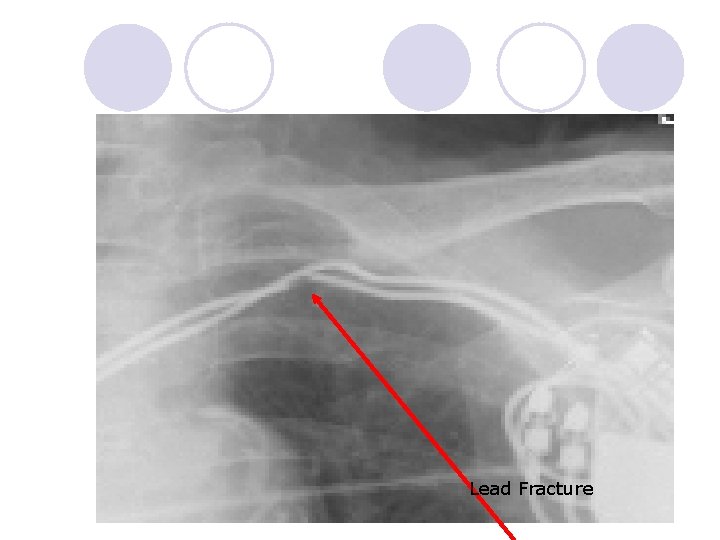

Complications of Device Implantation: q Pocket hematoma q Pocket infection q Pneumothorax q Cardiac perforation q Cardiac tamponade q Vascular damage l Lead dislodgement l Lead fracture l Lead infection l Inappropriate shocks

Laser Lead Extraction Program q. Implemented at UCH in 2008 by Chancey Weaver RN and Dr. Michelle Khoo M. D. q. First laser lead extraction in January 2009 q~30 leads extracted/year Reasons for a lead extraction: l l Fractured Leads Infected Lead(s) Non-functional leads/too many leads Regaining venous access

Lead Fracture